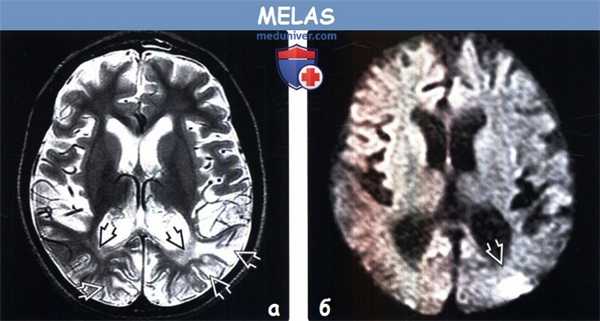

(а) МРТ-исследование в динамике, FLAIR, аксиальный срез: у этой же пациентки в возрасте 3,5 лет в левом таламусе определятся новая зона слабого повышения интенсивности сигнала. Кроме того, в коре/субкортикальном белом веществе затылочных долей визуализируется новая протяженная зона гиперинтенсивного сигнала и отека.

(б) МРТ, ДВИ, аксиальный срез: в пораженных зонах визуализируется снижение интенсивности сигнала, что указывает на подострый их характер. По данным протонной МР-спектроскопии (не представлены) было выявлено наличие лактата, что часто наблюдается в подострой стадии.